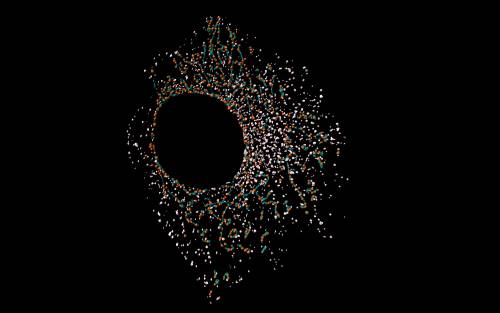

Cabe recordar que las mitocondrias son partes esenciales de la célula, que actúan como “centrales energéticas” de la misma. La unión de dos o más mitocondrias, así como la división de una mitocondria en dos unidades, son fenómenos habituales que se conocen como “dinámica mitocondrial” y son necesarios para el buen funcionamiento de estas estructuras, así como de la propia célula.